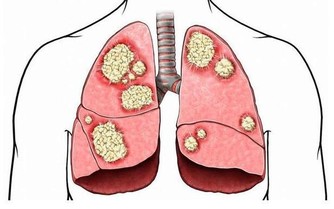

以下圖片來源 西醫認為: 缺鈣和脊椎的形變是最大的禍首。如果不及時治療,那麼,隨著鈣質的繼續流失、包括頸椎和腰椎兩大人體主要部位的形變,隨之而來的由骨折引起的死亡,腰椎、頸椎引起的腦供血不足和癱瘓等等,也會慢慢接近。